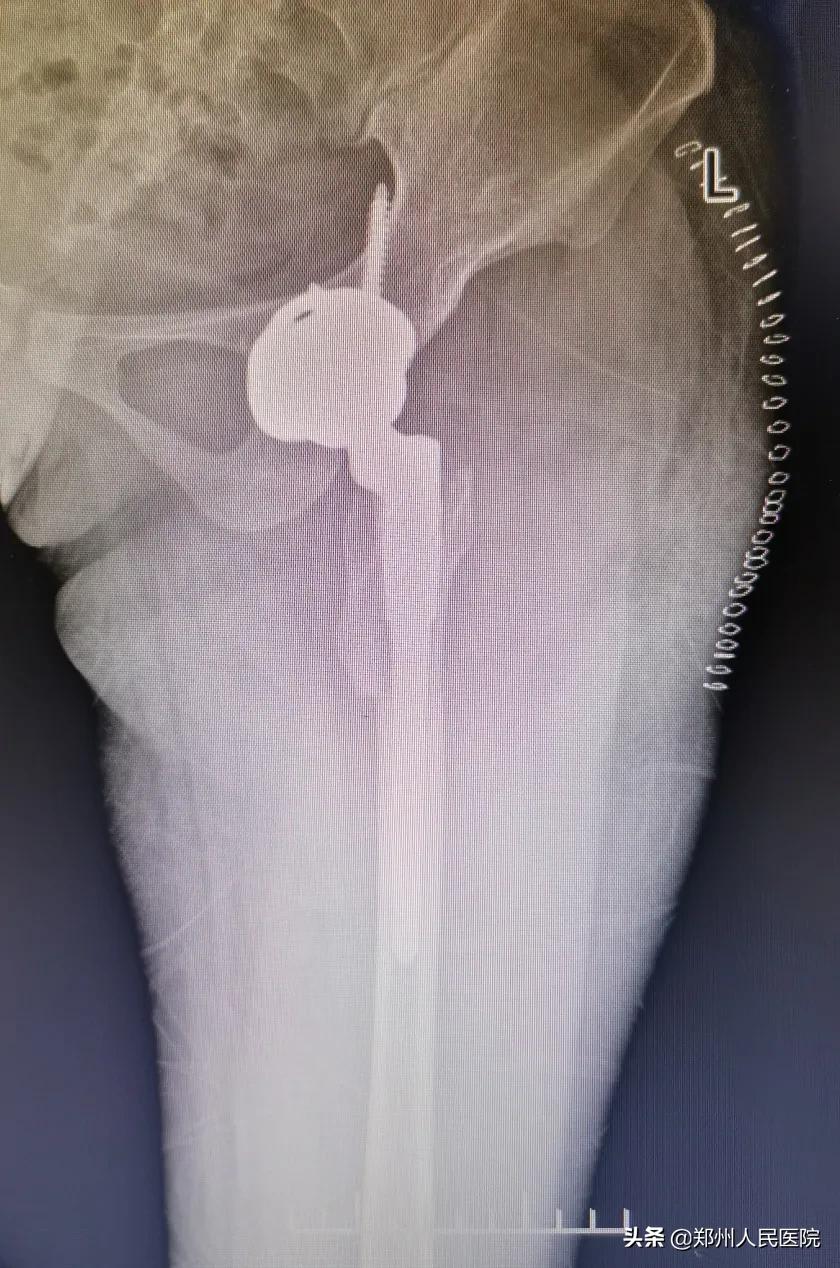

由于文文的髋关节发育不良,且髋关节磨损加重,建议其进行髋关节置换手术。

术前

“患者的情况已经不适合截骨手术,也就是保髋治疗。需要进行髋关节置换,放进一个人工的髋臼杯,再将股骨颈、磨坏的股骨头截掉,换上人工的股骨柄和股骨头,这样就形成了一个新的人工髋关节。通过手术可以解除患者髋关节的疼痛、改善走路一瘸一拐的症状。”尹万乐主任医师告诉小编。